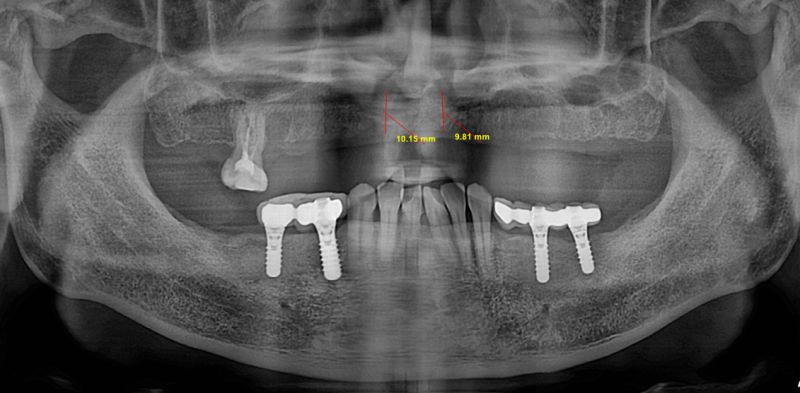

Good day to everyone, recently a gentleman came to my practice, requesting for implants to replace his upper non retentive complete denture. After taking the CBCT, i noticed that the remaining alveolar bone width and height are just sufficient for the all on 4 concept based on literature (5mm width and 10mm height). My surgical plan is as follows

2. Ridge expansion at planned implant site with densah bur and placement of 2 units 3.7x10mm at the anterior and another 2 units of 4.1x13mm implant at the posterior region followed by bone grafting with Ethoss. Temporisation with printed resin prosthesis.

Based off the limited info I see here it doesn’t appear the pt. Has sufficient bone for either of those procedures for long term success of the implants. Ridge augmentations possibly to improve success and have sufficient bone and biology for the implants or possible another route such as Zygo’s and/or ptero implants. Either way depending on your experience, skill, and comfort level this is definitely not a straight forward full arch case and has very little bone to work with for a predictable and successful outcome.